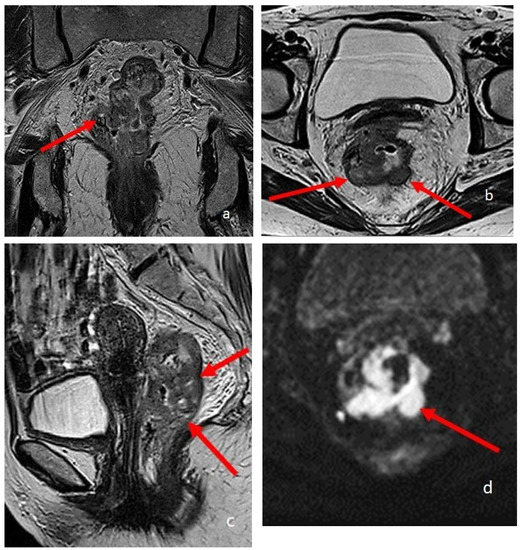

Figure 5.

MRI defecography sagittal T2-weighted images with endoluminal US gel, in a 62-year-old female with severe stipsis. (a) is rest phase, (b) is a straining phase (the arrows indicate a severe prolapse posterior compartment with invagination and anterior rectocele; mild prolapse of middle and anterior pelvic compartments), (c) is in evacuation phase (showing severe three-compartment pelvic prolapse with rectal invagination and anterior rectocele cystocele and colpocele (grade III)).